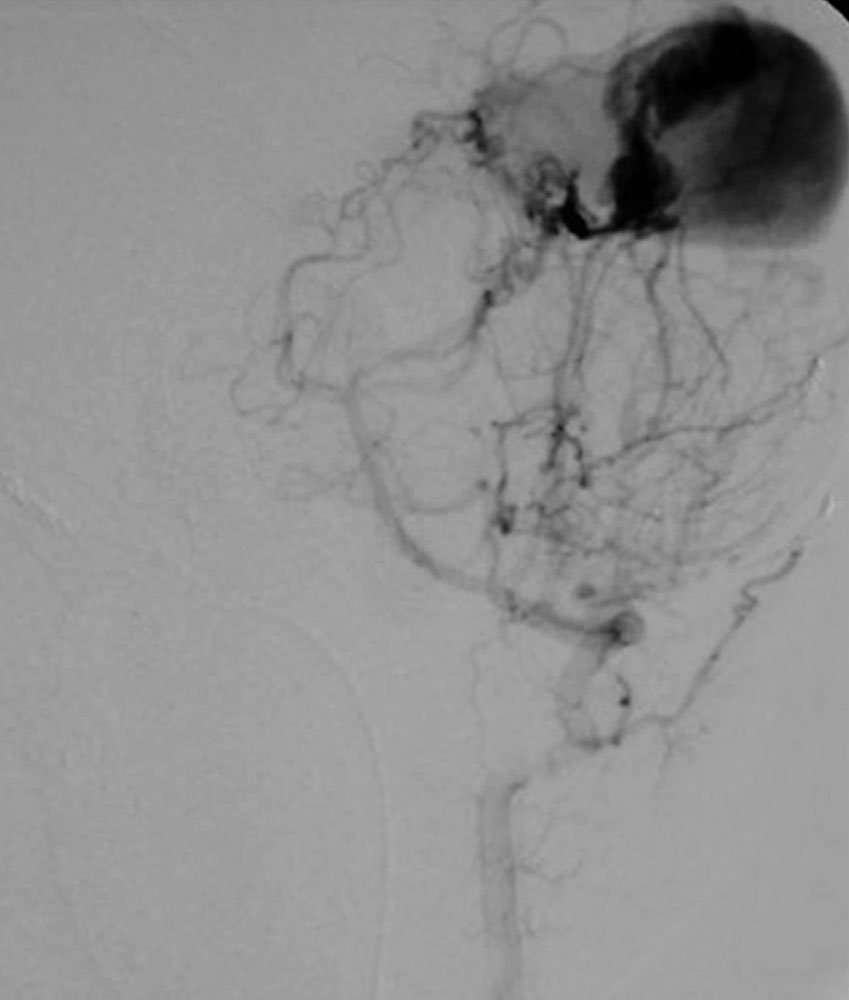

Weitaus häufiger sind kongenitale arteriovenöse Fisteln mit der hereditären hämorrhagischen Teleangiektasie vergesellschaftet, auch als Morbus Osler bekannt. Je nach zugrundeliegender Störung können bei bis zu 75 % der Betroffenen Fast-flow-Shunts zwischen Pulmonalarterie und Pulmonalvene diagnostiziert werden. Daraus können sich ein intrapulmonaler Rechts-Links-Shunt mit zerebralen paradoxen Embolien, Dyspnoe, Zyanose und Trommelschlegelfinger bis hin zur chronischen kardiopulmonalen Insuffizienz entwickeln.

Die prognostisch ungünstigsten Gefäßanomalien bei Patienten mit Morbus Osler entwicklen sich jedoch im Laufe des Lebens aus zunehmenden arteriovenösen Malformationen der Leber, die massive Ausmaße annehmen können und ebenfalls zu einer Rechtsherzbelastung bis zum Versagen führen können. Die früher dann häufiger versuchte Lebertransplantation wird heute meistens durch eine etappenweise durchgeführte selektive, segmentweise Embolisation der Leber-AVM vermieden.